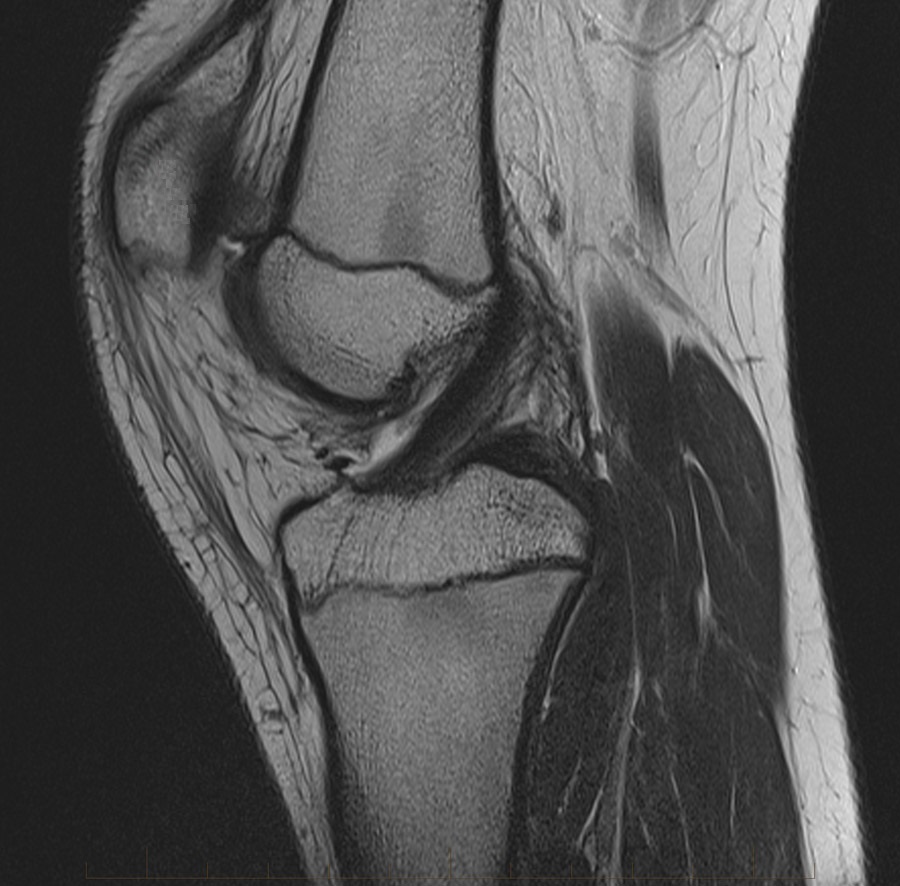

Four sets of test results are shown below. In Test 1 we compare models M1 – M6 to the proposed model M7 for two images which are hard to segment. The first is a CT scan from which we would like to segment the lower portion of the heart, the second is an MRI scan of a knee and we would like to segment the top of the Tibia. See Figure 9 for the test images and the marker sets used in the experiments. In Test 2 we will review the sensitivity of the proposed model to the main parameters. In Test 3 we will give several results achieved by the model using marker and anti-marker sets. In Test 4 we show the initialisation independence and marker independence of the Geodesic Model on real images.

In this test we give the segmentation results for models M1 – M7 for the two challenging test images shown in Figure 9. The marker and anti-marker sets used in the experiments are also shown in this figure. After extensive parameter tuning, the best final segmentation results for each of the models are shown in Figures 10 and 11. For M1 – M4 we obtain incorrect segmentations in both cases. In particular, the results of M2 and M4 are interesting as the former gives poor results for both images, and the latter gives a reasonable result for Test Image 1 and a poor result for Test Image 2. In the case of M2, the regularisation term includes the edge detector and the distance penalty term (see (4)). It is precisely this which permits the poor result in Figures 10(b) and 11(b) as the edge detector is zero along the contour and the fitting terms are satisfied there (both intensity and area constraints) – the distance term is not large enough to counteract the effect of these. In the case of M4, the distance term and edge detector are separated from the regulariser and are used to weight the Chan-Vese fitting terms (see (9)). The poor segmentation in Figure 11(b) is due to the Chan-Vese terms encouraging segmentation of bright objects (in this case), weighting enforces these terms at all edges in the image and near . In experiments, we find that M4 performs well when the object to segment is of approximately the highest or lowest intensity in the image, however when this is not the case, results tend to be poor. We see that, in both cases, models M5 and M6 give much improved results to M2 and M4 (obtained by incorporating the geodesic distance penalty into each). The proposed Geodesic Model M7 gives an accurate segmentation in both cases. It remains to compare M5, M6 and M7. We see that M5 is a non-convex model (and cannot be made convex [39]), therefore results are initialisation dependent. It also requires one more parameter than M6 and M7, and an accurate set to give a reasonable area constraint in (4). These limitations lead us to conclude M6 and M7 are better choices than M5. In the case of M6, it has the same number of parameters as M7 and gives good results. M6 can be viewed as the model M7 with weighted intensity fitting terms (compare (18) and (30)). Experimentally, we find that the same quality of segmentation result can be achieved with both models generally, however M6 is more parameter sensitive than M7. This can be seen in the parameter map in Figure 12 with M7 giving an accurate result for a wider range of parameters than M6. To show the improvement of M7 over previous models, we also give an image in Figure 13 which can be accurately segmented with M7 but the correct result is never achieved with M6 (or M3). Therefore we find that M7 outperforms all other models tested M1 – M6.

Test 2 – Test of M7’s sensitivity to changes in its main parameters. In this test we demonstrate that the proposed Geodesic Model is robust to changes in the main parameters. The main parameters in (20) are and . In all tests we set , which is simply a rescaling of the other parameters, and we set . In the first example, in Figure 12, we compare the TC value for various and values for segmentation of a bone in a knee scan. We see that the segmentation is very good for a larger range of and values. For the second example, in Figure 13, we show an image and marker set for which the Spencer-Chen model (M3) and modified Liu et al. model M6 cannot achieve the desired segmentation for any parameter range, but which can be attained for the Geodesic Model for a vast range of parameters. The final example, in Table 1, compares the TC values for various values with fixed parameters and . We use the images and ground truth as shown in Figures 12 and 13: on the synthetic circles image we obtain a perfect segmentation for all values of tested, and in the case of the knee segmentation the results are almost identical for any , above which the quality slowly deteriorates.